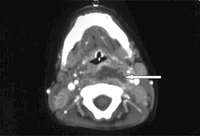

Abscesso retrofaríngeo

Tomografia computadorizada (TC) cervical demonstrando lesão com realce em anel

Philpott CM, Selvadurai D, Banerjee AR. Paediatric retropharyngeal abscess. J Laryngol Otol. 2004;118:919-926